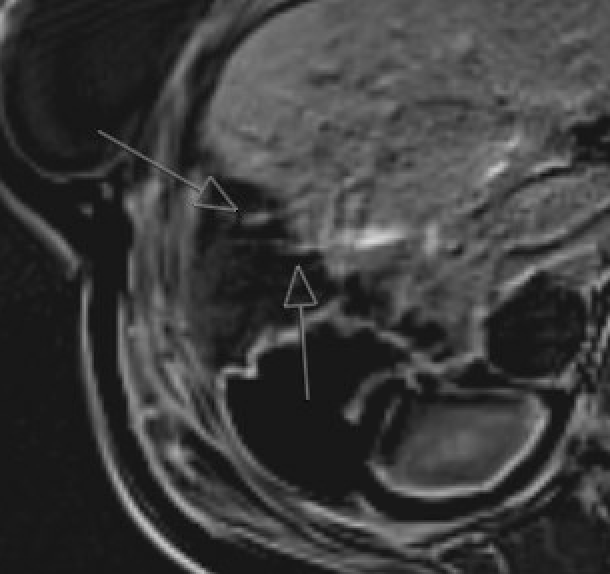

Pneumoperitoneum Subtle T2-hypointense foci in peritoneal cavity. Air-fluid levels. Susceptibility artifact on bSSFP and T1W GRE sequences. Can be easily missed — look for abnormal extraenteric T2-dark foci

MRI showing pneumoperitoneum with T2-hypointense foci and susceptibility artifact on gradient echo sequence

Pneumoperitoneum: T2-dark extraenteric foci, GRE susceptibility